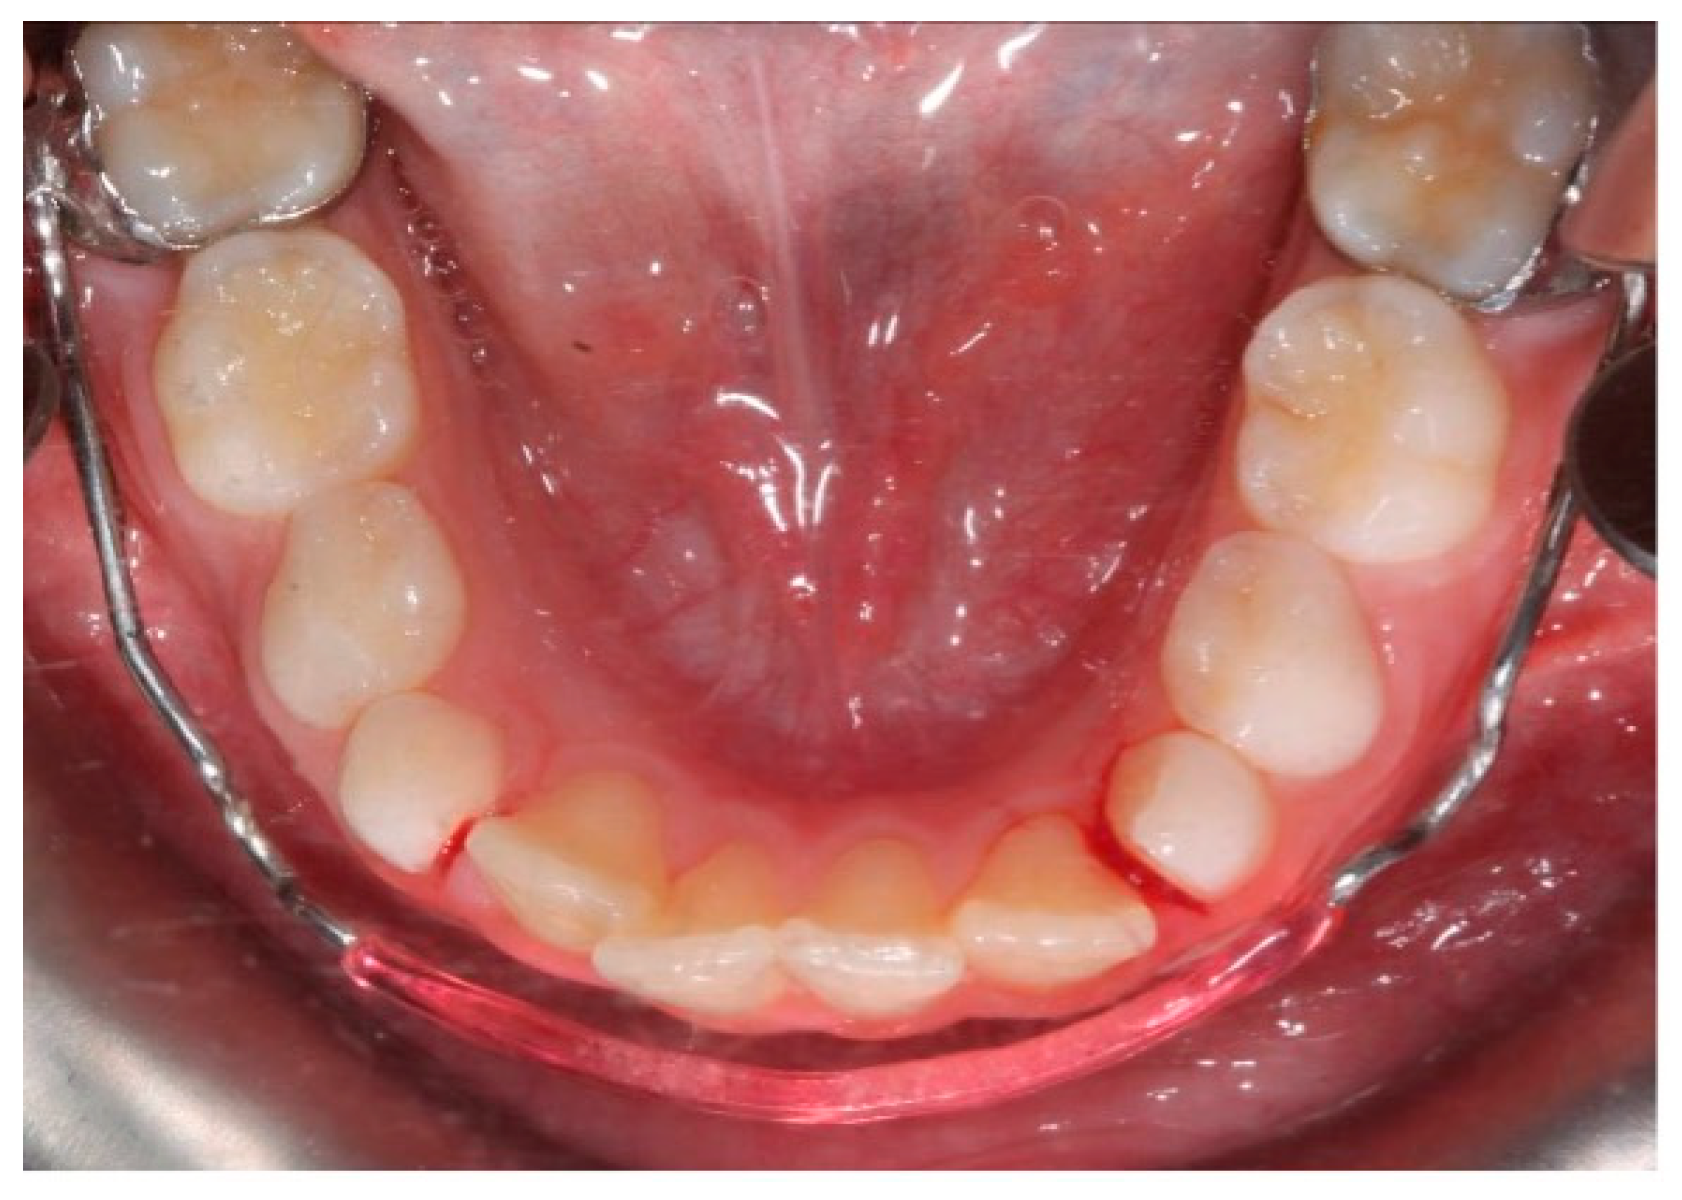

Crowding is a common orthodontic malocclusion with a strong hereditary tendency. It is caused by a variety of factors, including the impact of environmental and genetic factors on dental arch dimensions [1]. Dental crowding is defined as an inconsistency between tooth size and arch dimension that results in malocclusion; it occurs because of a lack of coordination between tooth size and arch dimensions [2,3,4,5]. The lower incisors are the teeth most frequently involved [6,7,8] (Figure 1).

Figure 1. Crowding of the permanent mandibular incisors.